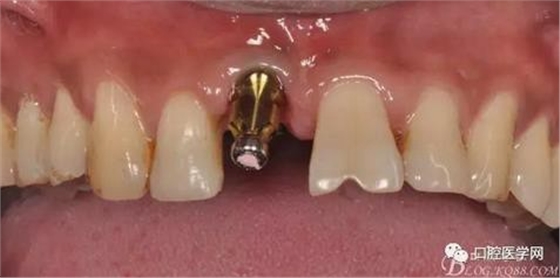

圖8 術后即刻臨時冠修復

圖9 三個月后袖口形成正位照

圖19 口內修復基臺正位照

圖20 口內修復基臺正位照